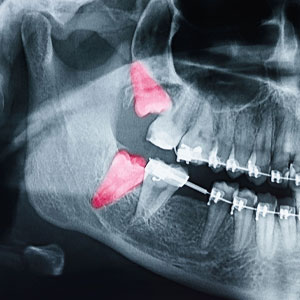

We provide a comprehensive range of oral and maxillofacial procedures to address a broad spectrum of needs. As an experienced, highly skilled oral and maxillofacial surgeon in Miramar Beach, Dr. Eric Scheufler is knowledgeable in all areas of head and neck anatomy and is specialty trained to provide the precise care you or any member of your family requires to support optimal oral health, function, and appearance.

From the provision of emergency care to address a range of oral and facial injuries to performing all types of dental extractions and bone grafts as well as other hard and soft tissue procedures, the placement of dental implants and TMJ disorders, our oral and maxillofacial surgeon in Miramar Beach provides the highest quality of skilled, reliable care.